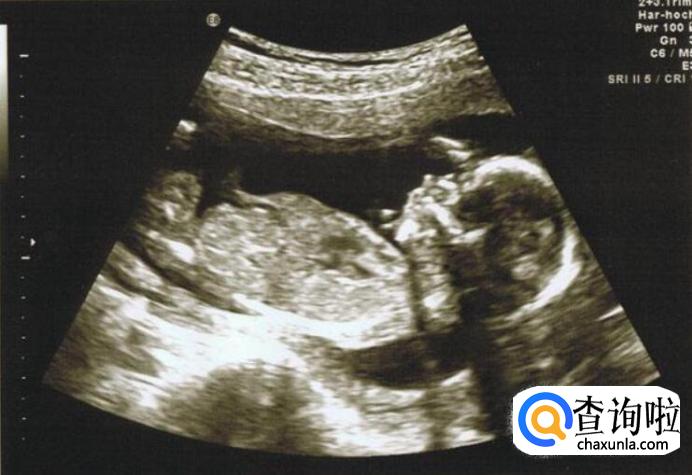

对于一般人来说,看B超图像是一件很茫然的事情,那么接下来我就教大家如何看胎儿的B超图像和如何判断胎儿性别。

看胎儿形状。

妊娠中的妈妈们,一般会在怀孕两个月的时候前往医院使用B超进行孕检。这时候可以通过胎儿的最初形状判断性别。如果宝宝的形状是长型的,像茄子或长条状的,那么很有可能是男宝宝,若是椭圆或是圆型,那么可能是女宝宝。

如果孕晚期,也可以胎儿的胎位,面朝外的一般是女宝宝,背朝外的一般是男宝宝。